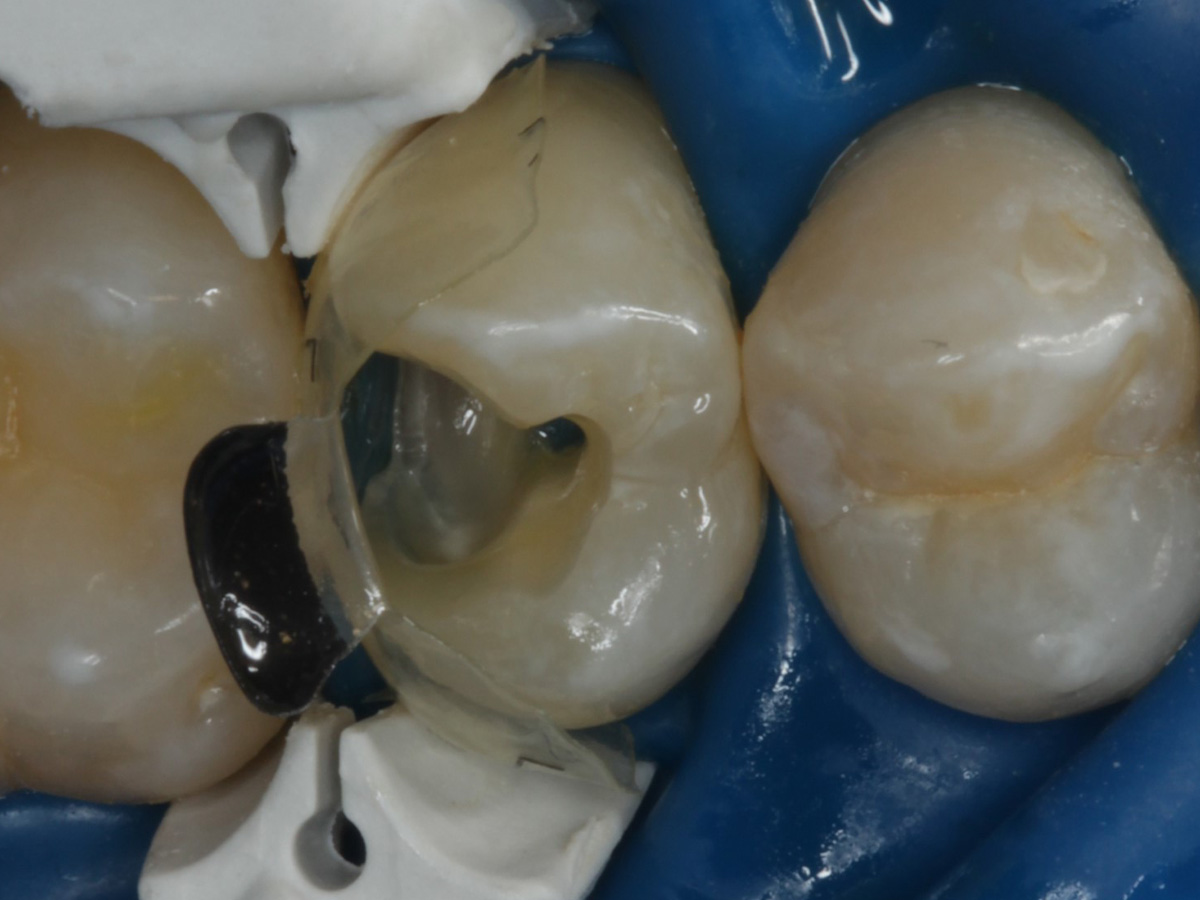

Abbildung 10

Nach Spray und Trocknung der Kavität: perfekte Adaptation der Matrize insbesondere tief subgingival